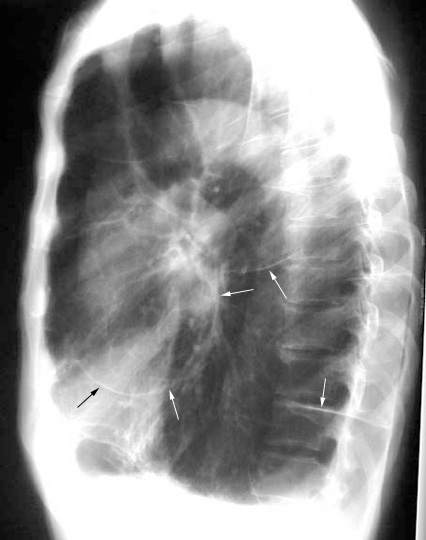

Case 9

Follow up

Spine

Neck

Labeled Image What are the pulmonary manifestations of Ankylosing spondylitis?